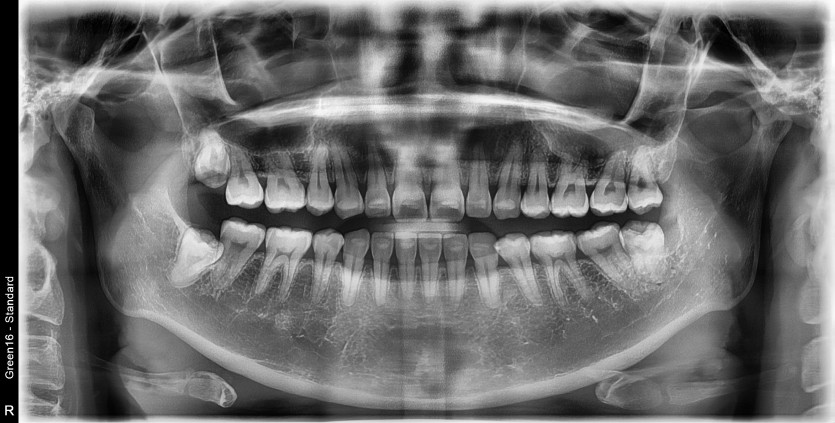

#28, 38 사랑니 발치

구강 외과 전문의가 당일 발치했습니다.